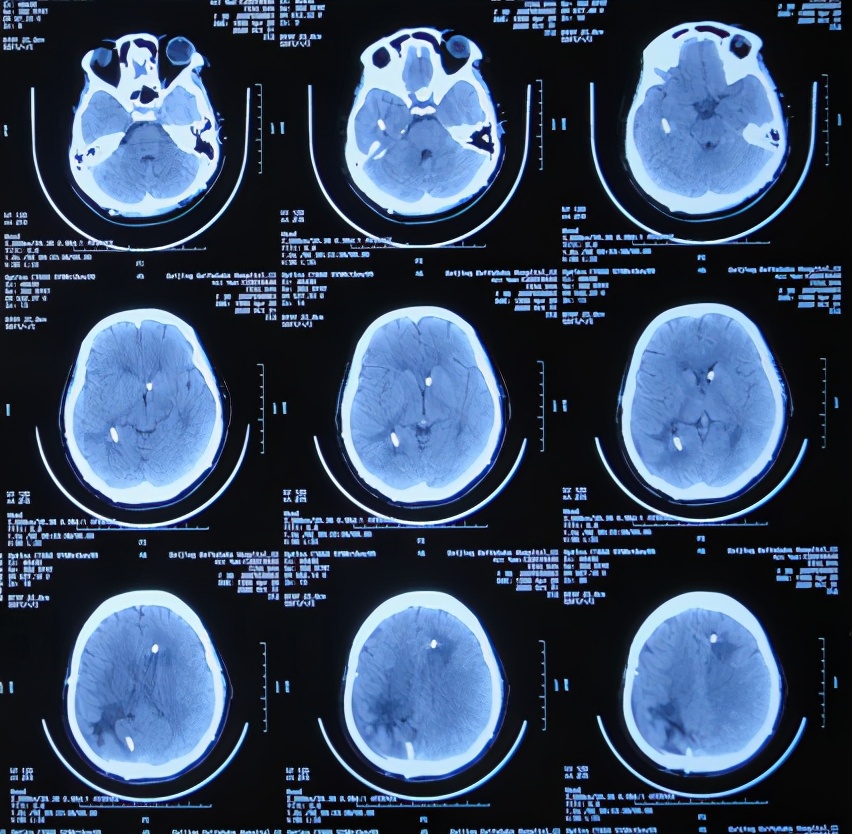

患者于2020年4月2日,在公司上班时突发头痛呕吐,急诊至陕西省西安市某二级医院,急诊查头颅CT检查示右顶叶脑出血破入脑室( 图-1 ),全脑血管造影示脑血管畸形(片子丢失);进行了开颅脑血管畸形切除术+去骨板减压术,术中留置引流外管;术后当天转入ICU继续治疗。

图-1: 2020年4月2日头颅CT